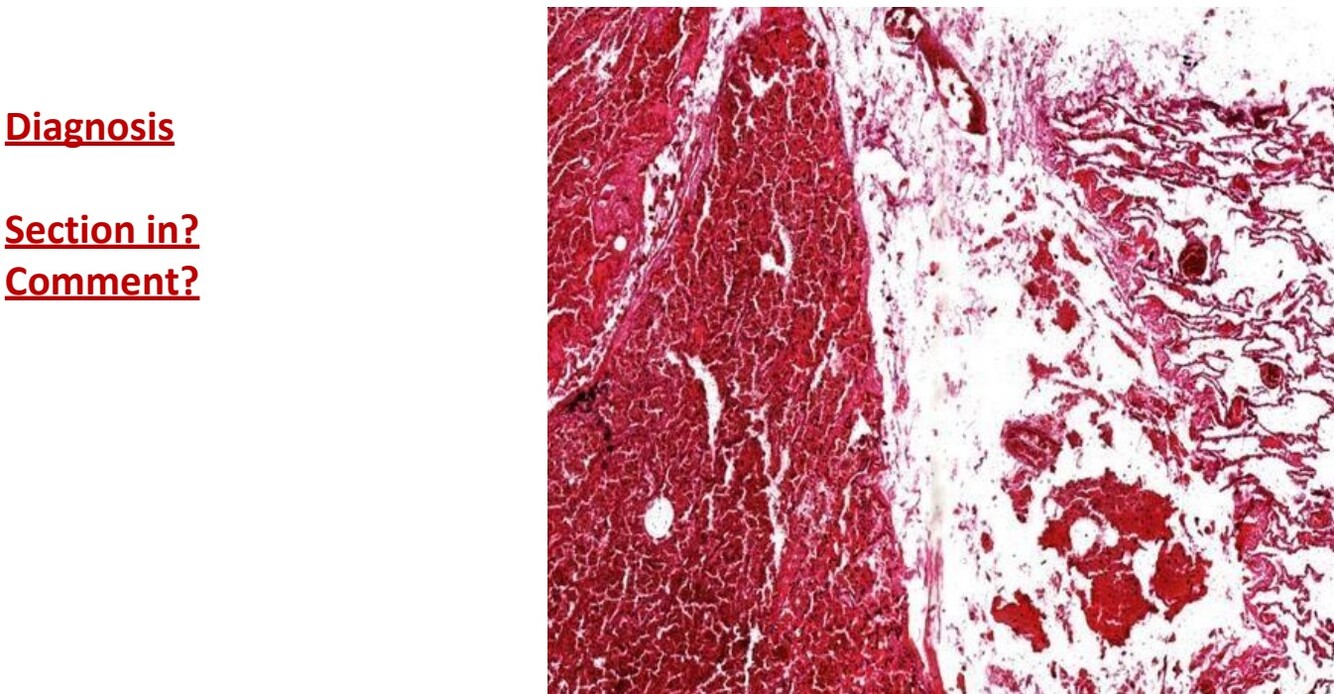

Infarction in spleen

Section in spleen

Infraction shows structureless pink area. Red and white pulp appear as GHOSTS

3 zones from left to right: infarction, congestion and normal zone